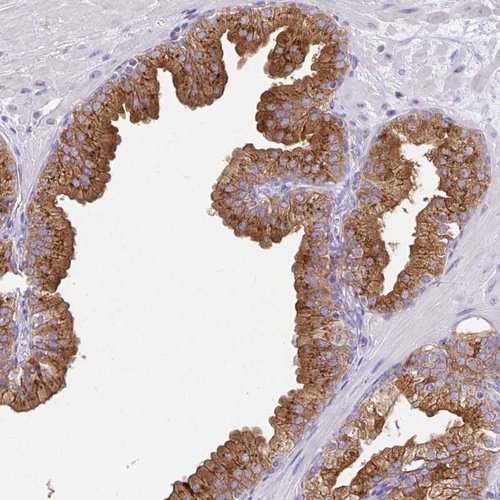

Immunohistochemical staining of human prostate shows strong cytoplasmic positivity in glandular cells.